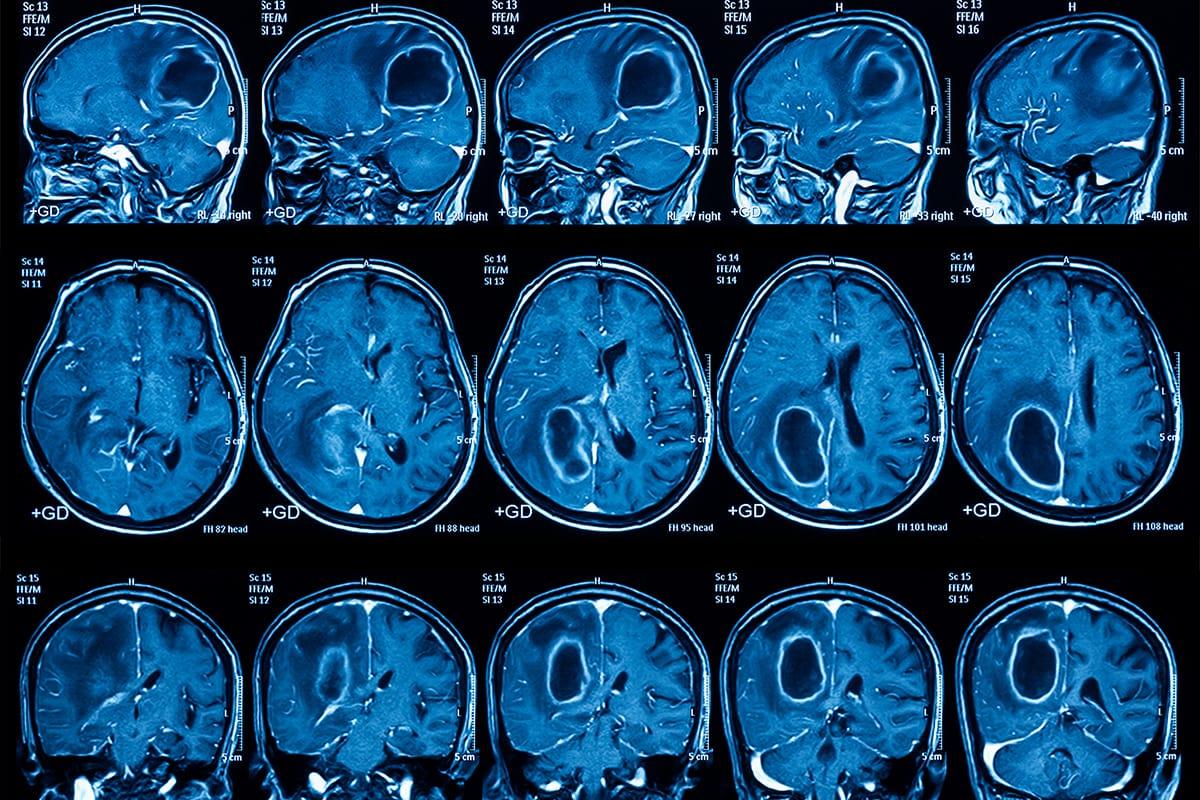

Il glioblastoma è uno dei tumori cerebrali maligni più aggressivi e a più rapida crescita. Sebbene raro, è il tumore cerebrale maligno primario più comune negli adulti, colpendo circa tre persone su 100.000. È resistente al trattamento e spesso recidiva. Gli scienziati lo hanno definito un "tumore freddo" per la sua capacità di nascondersi al sistema immunitario. Sebbene gli scienziati possano in qualche modo smascherare questo travestimento, i farmaci attuali si degradano rapidamente e possono essere somministrati direttamente al cervello attraverso iniezioni rischiose. I ricercatori del Siteman Cancer Center dell'Università di Washington hanno adottato un approccio diverso, sviluppando un metodo non invasivo che attiva la risposta immunitaria per attaccare il glioblastoma. In collaborazione con i chimici della Northwestern University, hanno creato speciali strutture di dimensioni nanometriche (nanoparticelle) sotto forma di acidi nucleici sferici (SNA) a base d'oro. L'idea era di somministrarle all'organismo attraverso il naso, sotto forma di gocce nasali. Le nanoparticelle viaggiano attraverso la mucosa nasale, seguendo le vie nervose, fino al cervello e, al suo interno, all'ambiente tumorale. Una volta che le nanoparticelle raggiungono il tumore o almeno si avvicinano ad esso, attivano i macrofagi, le cellule immunitarie che solitamente proteggono il glioblastoma, in modalità antitumorale. Si innesca una reazione immunitaria: viene attivata una via immunitaria intrinseca (la via STING), che è una delle vie di risposta immunitaria dell'organismo a virus e tumori.